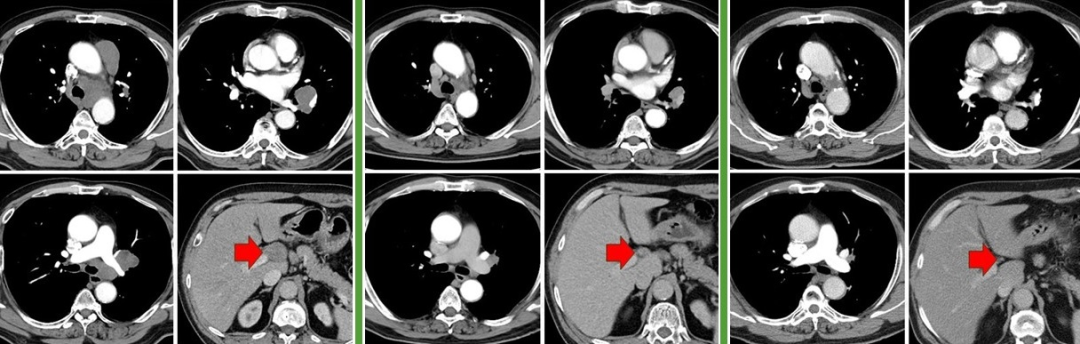

58岁,男,吸烟史40年×30支,2020.6出现咳嗽,CT见左肺门占位,气管镜取病理示小细胞癌,cT1cN0M0 IA3期,于当地医院行EP方案化疗4周期,病灶缩小,序贯胸部放疗。2021.4复查见左肺新发占位,又行TP方案化疗2周期,评效PD。2021.9来我中心就诊,气管镜再活检示小细胞癌,rT1cN1M0 IIB期局限期。予EP方案化疗2周期,评效SD,改安罗替尼+EP方案化疗4周期,评效SD-,后安罗替尼维持治疗。2023.9复查CT见左肺病变增大、左下肺部分不张,气管镜见左下肺开口狭窄,活检见肿瘤细胞,未行免疫组化。全身检查未见远处转移,行斯鲁利单抗+白蛋白紫杉醇化疗4周期,评效PR,后斯鲁利单抗维持治疗至今(17周期)。截至2025.2.20

治疗小结:1.EP×4序贯胸部放疗,PFS 10个月;

2.TP×2,PFS 1.5个月;

3.EP×2、安罗替尼+EP×4、安罗替尼,PFS 24个月;

4.斯鲁利单抗+白蛋白紫杉醇×4、斯鲁利单抗×17+,PFS 17个月+。

图:左起依次为三线治疗前、三线治疗后、四线治疗前、末次随访